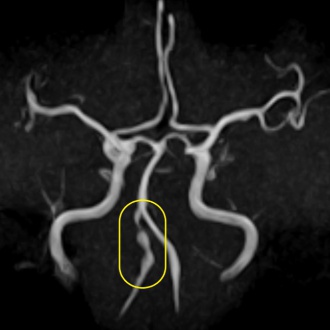

脳動脈解離とは脳の動脈の壁が裂け、血管内の血液が血管の壁の中にたまる病気です。頭痛のみの場合も多いですが、ひどくなると血管が細くなり血管が詰まって脳梗塞を起こしたり、血管の壁が破裂してくも膜下出血を起こすこともあります。

脳動脈解離は首の骨から頭に入る動脈で起きることが多く、片側の後頭部が突然痛くなります。すぐに対応すれば、脳梗塞やくも膜下出血を予防することができます。突然のひどい頭痛が続く場合は、早めに受診しましょう。

なお、写真の黄色で囲った部位が血管解離した部位です。